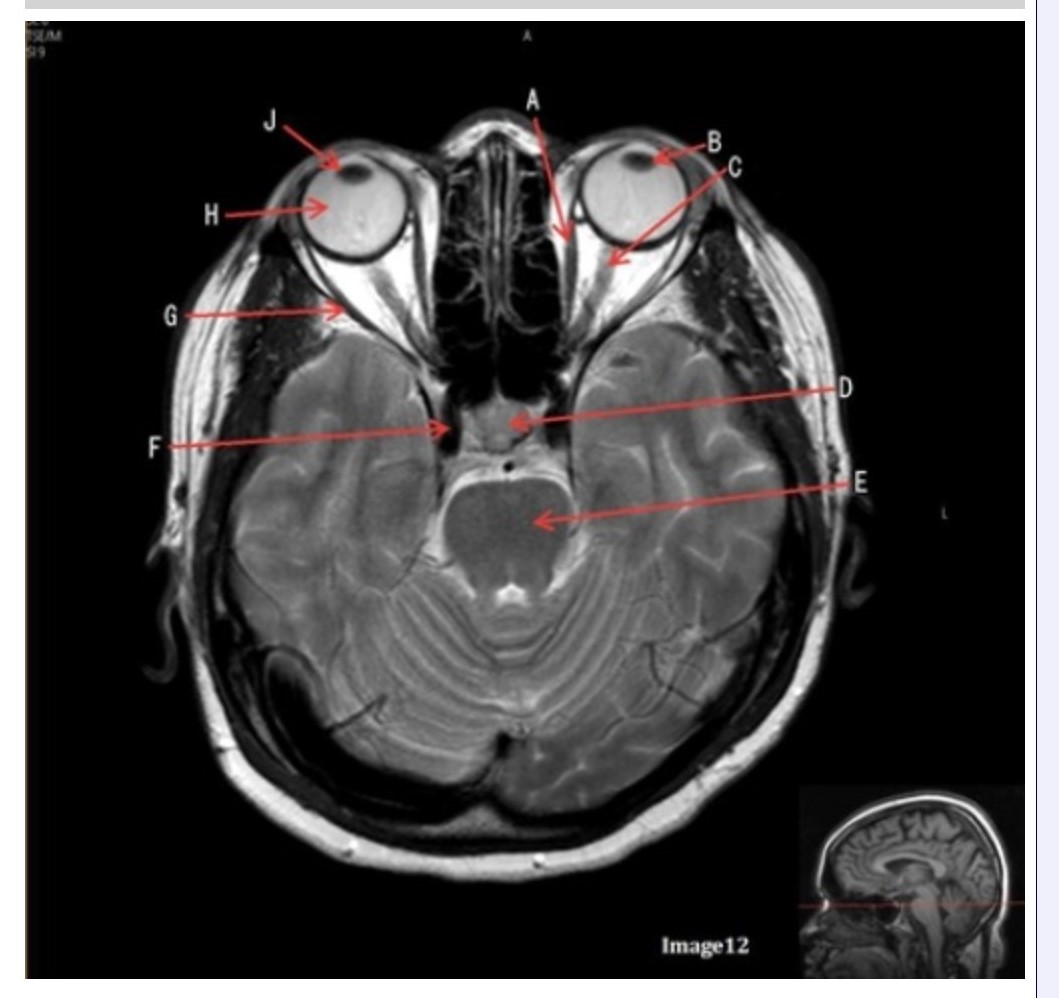

Letter H in Image 12 is pointing to:

A. Lens

B. Lateral rectus muscle

C. Medial rectus muscle

D. Internal carotid artery

E. Globe

Letter B in Image 12 is pointing to:

A. Left optic nerve

B. Lateral rectus muscle

C. Medial rectus muscle

D. Lens

E. Midbrain

Letter J in Image 12 is pointing to:

A. Globe

B. Lateral rectus muscle

C. Medial rectus muscle

D. Right lens

E. Left lens

Letter F in Image 12 is pointing to:

A. Lens

B. Lateral rectus muscle

C. Medial rectus muscle

D. Internal carotid artery

E. Globe

Letter C in Image 12 is pointing to:

A. Left optic nerve

B. Lateral rectus muscle

C. Medial rectus muscle

D. Lens

E. Midbrain

Letter D in Image 12 is pointing to:

A. Optic nerve

B. Pituitary gland

C. Globe

D. Lens

E. Midbrain

Letter G in Image 12 is pointing to:

A. Lens

B. Lateral rectus muscle

C. Medial rectus muscle

D. Internal carotid artery

E. Globe

Letter E in Image 12 is pointing to:

A. Optic nerve

B. Pituitary gland

C. Globe

D. Pons

E. Left lens